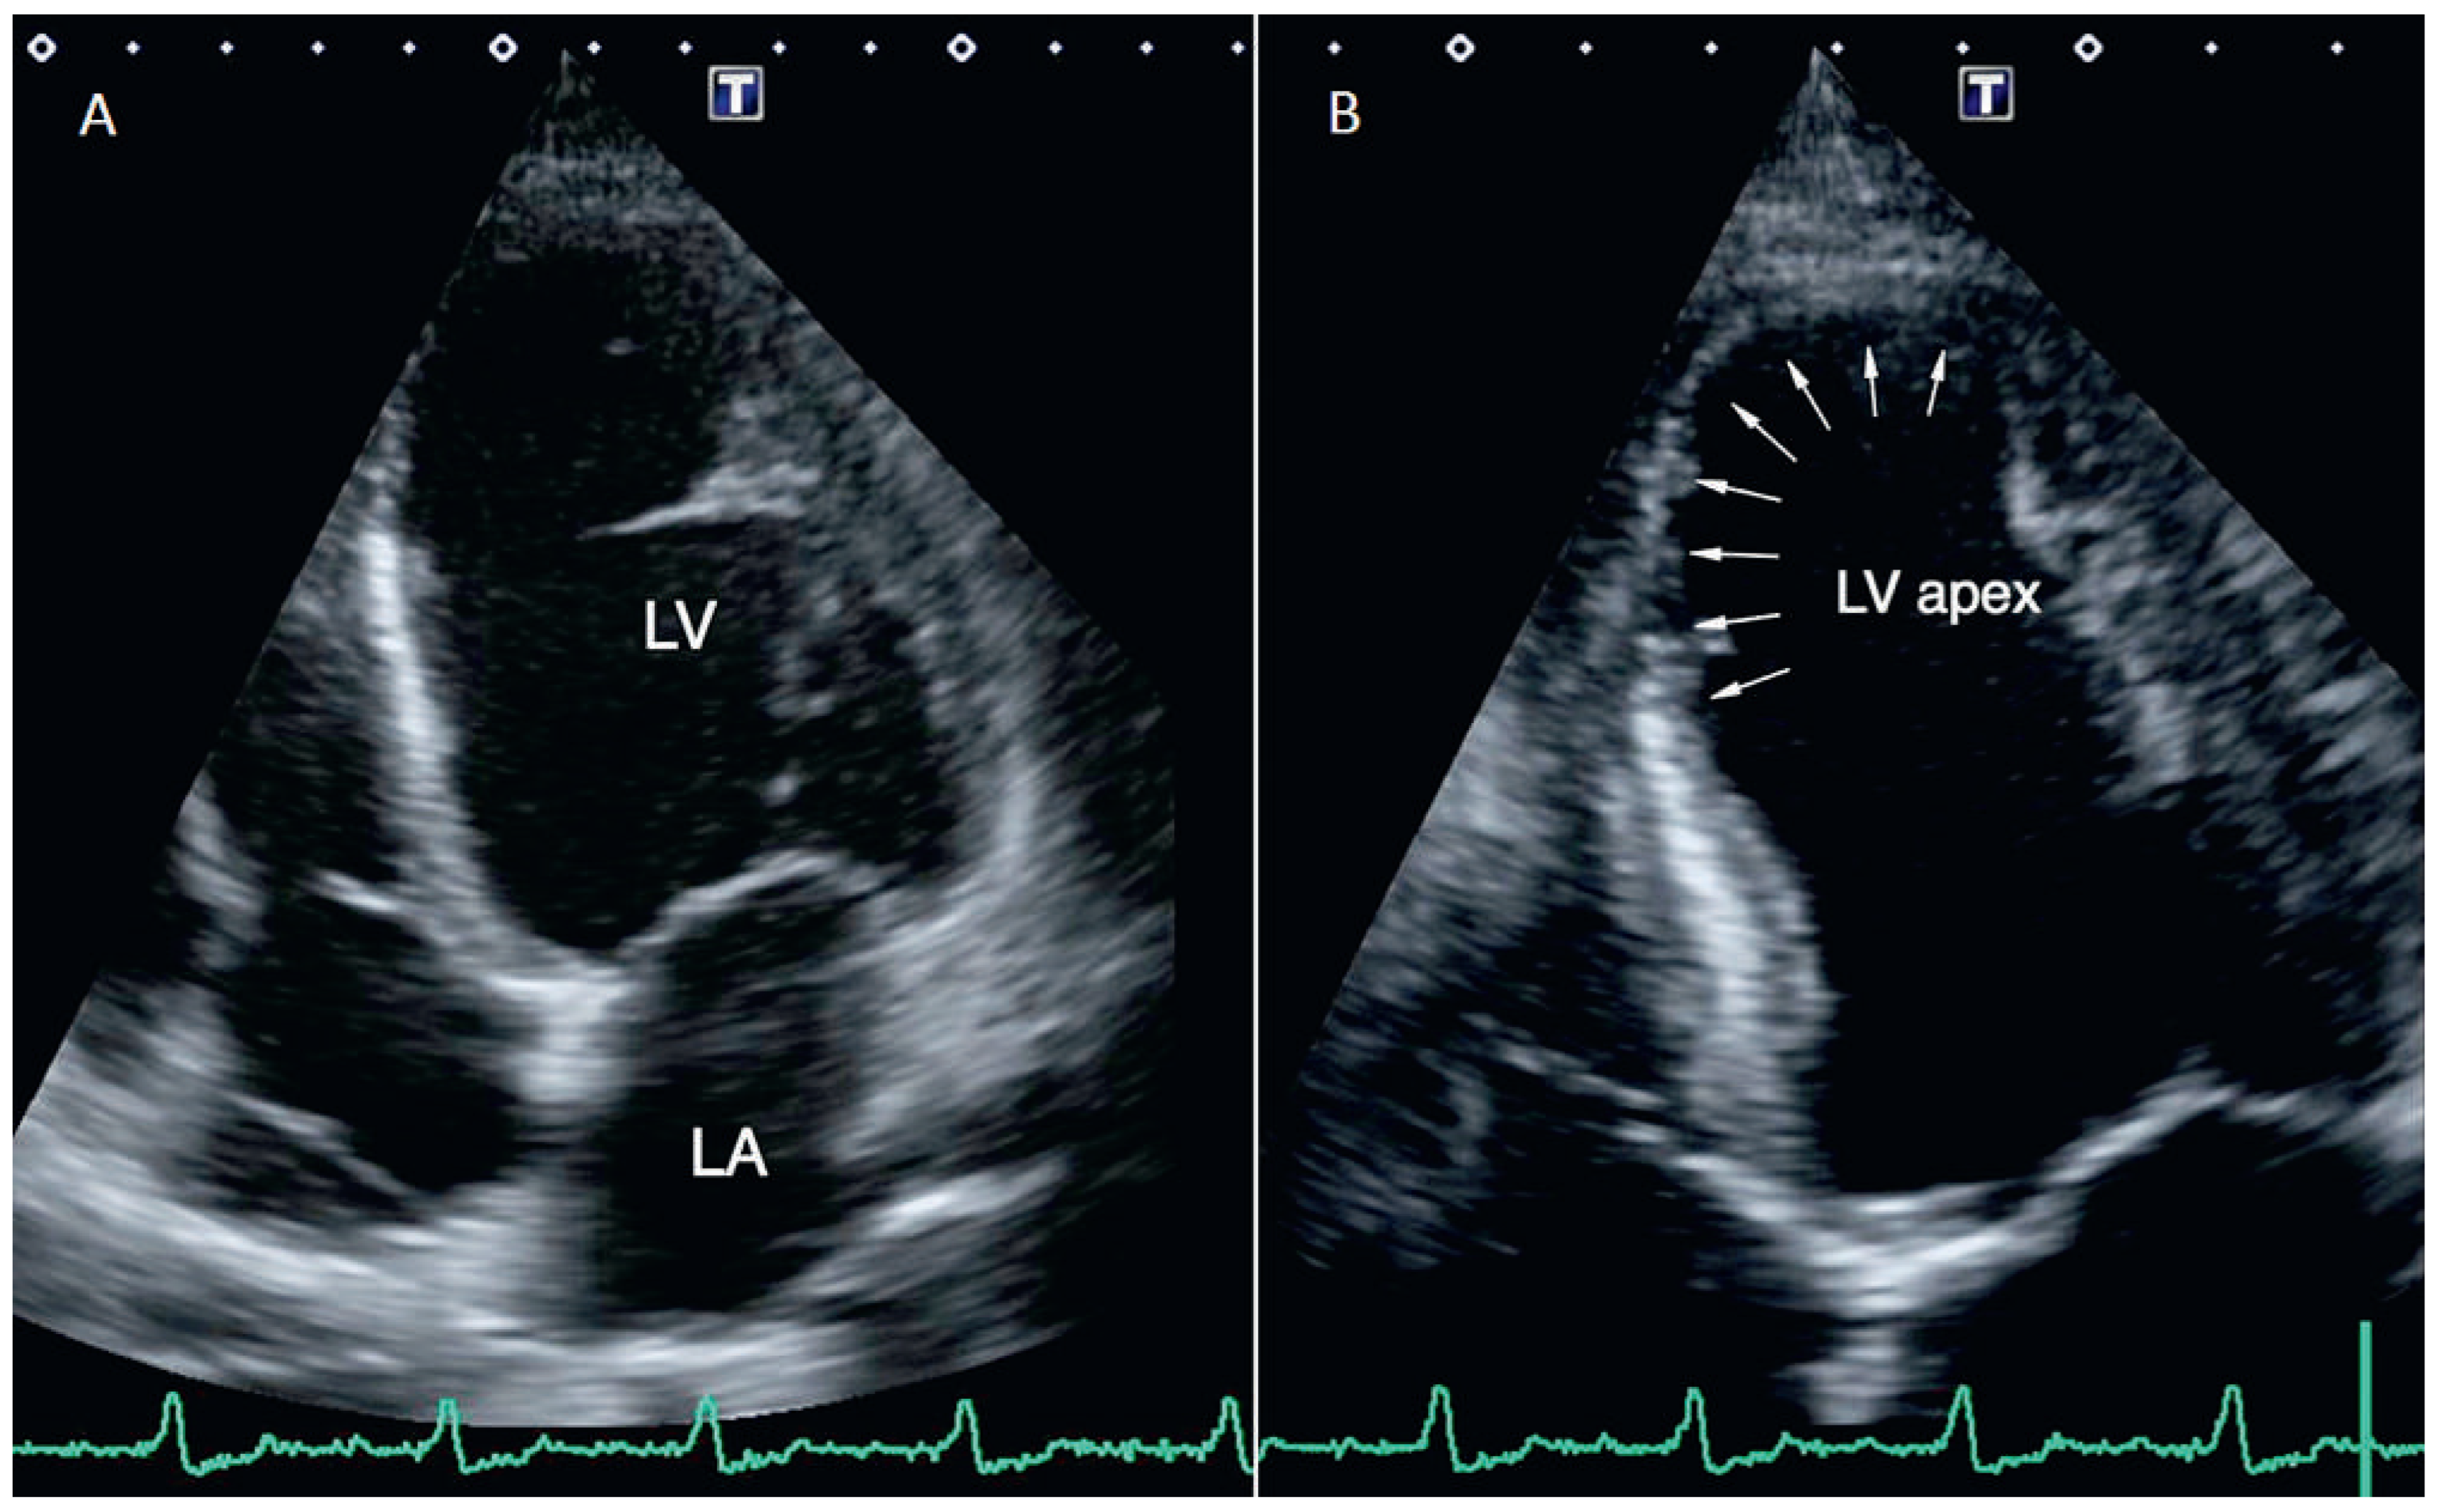

A 49-year-old Bolivian woman presented with progressive fatigue, dyspnoea NYHA II, and mild leg oedema. Her cardiovascular medical history was unremarkable. Originating from La Paz in Bolivia, she had been living in Switzerland for the past 14 years and had never returned to her home country. Apart from permanent bradycardia of 30 bpm and mild leg oedema, the clinical examination was normal. We diagnosed alternating second degree (type Mobitz 2) and complete atrioventricular block (AVB) with a narrow QRS complex without bundle branch block (Figure 1). Echocardiography in a bradycardial escape rhythm (32 bpm) revealed a slightly dilated left ventricle (end diastolic volume index [EDVI] 80 ml/m2) with a preserved systolic function (left ventricular ejection fraction [LVEF] 57%) and an apical ventricular aneurysm (Figure 2). The troponin level was normal and other signs of coronary heart disease were absent. For both rheumatic syndromes and Lyme disease, negative serologic test results were obtained. A chest x-ray and clinical examination did not show any signs of sarcoidosis.

Heart related clinical findings after years or even decades of chronic infection often include dilated cardiomyopathy and arrhythmia. About 17–28% of all infected patients develop heart failure. Dilatation of the left ventricle and apical aneurysms are echocardiographic key features for confirmation of the diagnosis [4]. In end stage disease patients present with fullblown dilated cardiomyopathy and corresponding heart failure.

Figure 2. Echocardiography 4-chamber apical view after pacemaker implantation. (A) Dilated cardiomyopathy (enddiastolic freeze-frame). (B) Ventricular aneurysm (arrows) in the apex of the left ventricle (endsystolic freeze-frame). LV = left ventricle; LA = left atrium; LV apex = apex of left ventricle.